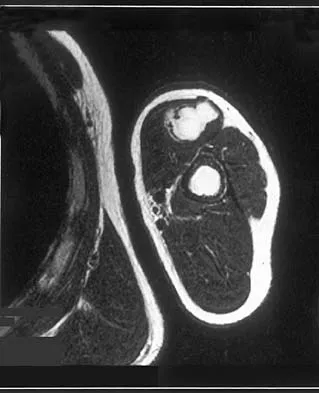

A 43-year-old woman has had pain in the left hip for the past 2 months. A radiograph, CT scan, MRI scan, and biopsy specimens are shown in Figures 16a through 16e. What is the most likely diagnosis?

Explanation